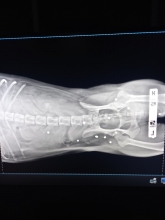

Оренбурженка связалась с волонтёрами приюта "Я - Живой". Удалось найти автомобиль, свозить животное в ветклинику. Как оказалось, её расстреляли из охотничьего ружья. В теле обнаружили 19 дробин. Не было практически ни одного живого места: повреждены голова, лапы, позвоночник, грудь, горло, живот, глаз. Врач отметил, что если бы стреляли с более близкого расстояния, то шансов выжить у бедной собаки не было бы...

Кроме того, собака была беременна. Щенков она потеряла. Белоснежку, как назвали пострадавшую собаку, ждут операция и длительное восстановление.

Вопрос об операции будет решаться после того, как ее состояние стабилизируется, ей нужно отогреться, так как два дня она пролежала в снегу, проколоть антибиотики, подождать сокращения матки и остановки кровотечения. Одно точно: левый глаз, залитый кровью, видеть не будет, дробь повредила его полностью, - отметили волонтеры.